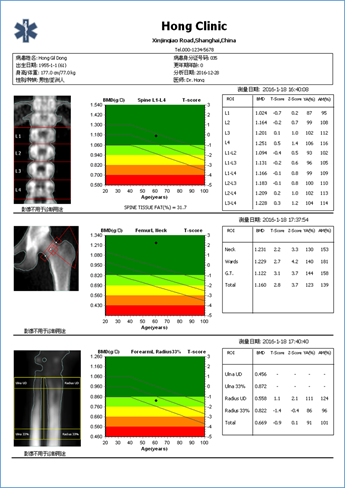

▎四、多部位影像集成报告

KD-GRAND具备全中文多部位影像集成报告系统,可将所有检测结果打印在一张报告上进行评估,简洁明了,便捷高效。

图表背景是三种颜色表示的骨折危险性的评估:绿色及浅绿:T-score在-1以上,骨密度正常;黄色:T-score在-1~-2.5之间,骨量减少;浅红及红色:T-score在-2.5以下,骨质疏松。